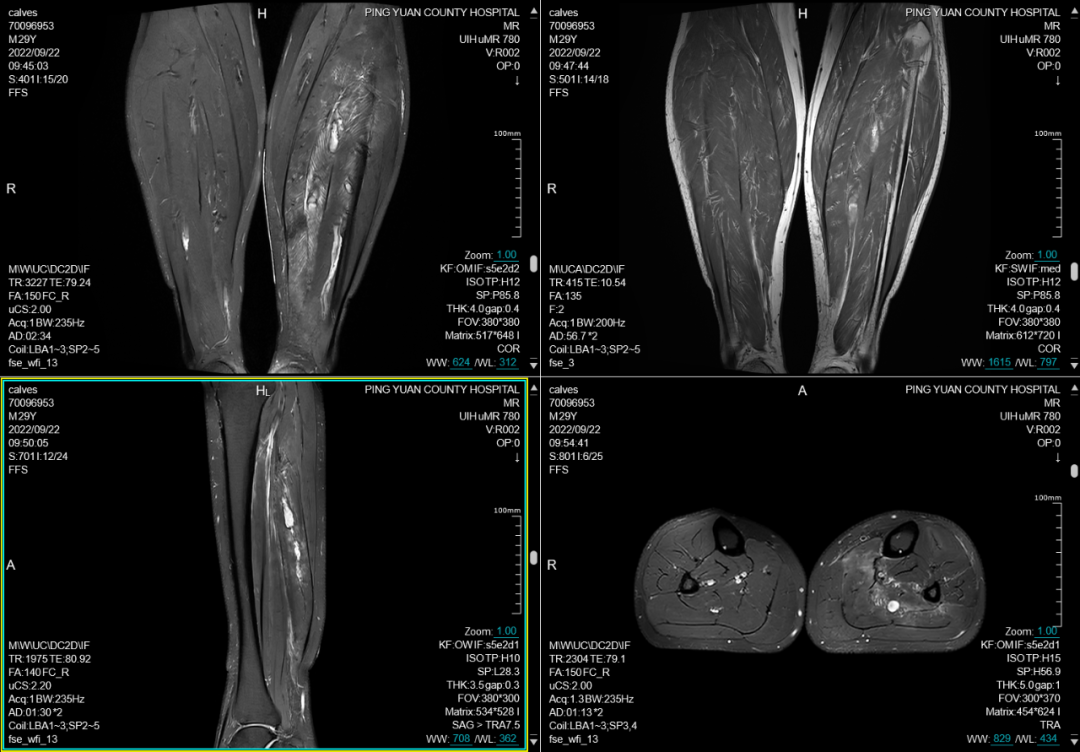

六、在四肢及关节检查方面:图像更清晰,后处理功能更丰富

MRI彻底变革了骨骼肌肉结构的成像,主要应用于创伤、关节炎、肿瘤和感染等方面。在创伤方面可显示平片或CT不能显示的病变如骨挫伤或骨小梁骨折,隐匿性骨折平片甚至CT易漏诊,而MRI能清晰显示。MRI是无创评估关节内软骨的最佳检查手段,能清晰观察软骨细微变化。

(小腿平扫)